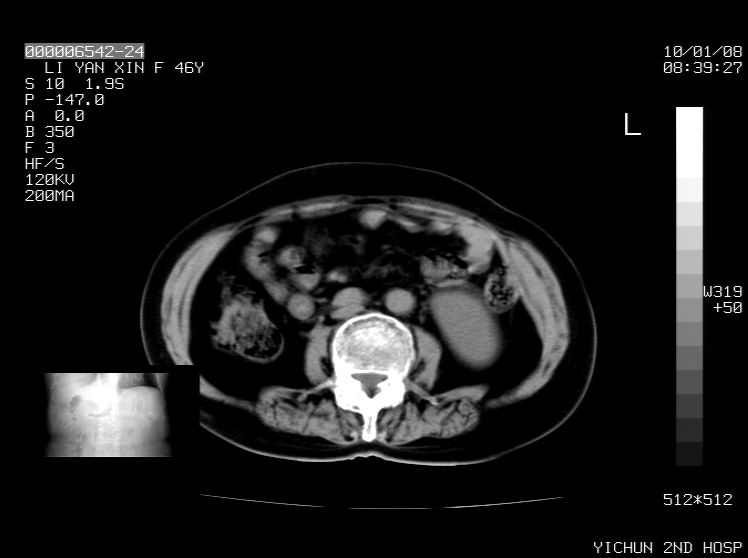

右侧膈膨升,胆囊壁厚,右侧肾脏缺如,增强,腔静脉旁是否是移位肾

肝脏变异致膈升高,肝左叶肝内胆管结石.右肾萎缩,左肾代偿肥大.

胆囊ct未见确切异常,请结合b超。右侧肾窝未见确切肾脏影,右肾萎缩?异位?

右侧膈膨升,肝内钙化灶,胆囊壁厚,右肾萎缩或发育不良。

右侧膈膨升,胆囊壁厚,右侧肾脏缺如。病史?